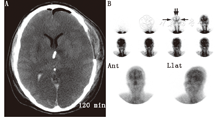

(4)脂溶性放射性药物。从20世纪80年代中期开始[72,73,74],脂溶性放射性核素99Tcm-HMPAO[75,76,77,78,79]和99Tcm-bicisate[47,48,80]跨越血-脑屏障经相关代谢后滞留于脑间质,从而可用于诊断脑死亡。即使在代谢功能紊乱时,此类探针也可滞留于脑间质[78,79]。其与4支脑血管对比造影术有较好的相关性[81]。通过显像可获得早期血流相和随后的血池相;但只要其中任何一相有血流存在,则均不支持脑死亡诊断(图3,图4)。99Tcm-HMPAO分解较快,需在30 min内注射[82]。随后开发的稳定制剂具有更长的贮存期,但注射时需先通过直径为0.45 μm的过滤装置以排除颗粒物质[83];必须注意确保过滤不妨碍足够的"弹丸"注射剂量。

静态血池相更为灵敏,且重要的是其对后颅窝的评估能力(图5);动态血流相主要反映脑前部情况,不能反映血池相信息[79,84]。临床研究主要使用延迟显像来评估脑血流灌注情况[77,78,85,86]。de la Riva等[79]的研究表明血流相无法显示的血流情况在静态血池相中小脑灌注很清晰。此外,由于血池相较血流相可以获得更高的放射性计数,因此图像的灵敏度更高。血池相对"弹丸"注射技术和注射时间的依赖性较小;还可进行重复显像及断层显像[87,88,89]。除外血池相无显像的罕见情况,99Tcm-HMPAO准备失败会导致动态血流图像的摄取值持续残留[20,78,79,80,81,82,83,84,85,86,87,88,89,90]。